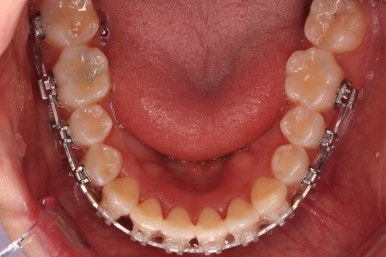

다시 이번 환자분으로 돌아가, 입 안모습을 보시겠습니다.

부산무턱교정 키다리아저씨치과에서 처음 내원하셨을 당시의 입 안의 모습입니다.

아래턱이 작아서 상대적으로 윗니들이 많이 돌출되었고, 뻐드러져 있습니다. 윗니들이 배열되어 있는 형태도 V자에 가깝게 입천장이 좁은 양상입니다.

장치를 부착하였습니다.

이번에 부착한 장치는 엠파워 클리어라고 하는 자가결찰 세라믹장치 입니다.

세라믹이기 때문에 덜 보이며 자가결찰 장치이기 때문에 초기에 가지런해지는 속도가 빠르고 통증이 덜한 장점이 있습니다.